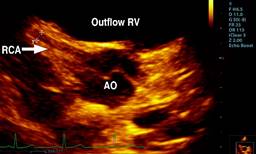

The parasternal short-axis view of the aortic root showed the right coronary artery (RCA) and left coronary artery (LCA) in their appropriate anatomical positions, with the proximal segment of the RCA exhibiting a Z score of 0.2 (Figure 1). However, the suprasternal longitudinal view identified an abnormal vascular structure with anterograde flow descending into the right branch of the pulmonary artery (RBPA) (Figure 2). The suprasternal short-axis view illustrated an anastomosis at the proximal segment of the RBPA, characterized by continuous, pulsatile flow, a maximum recorded velocity of 2.8 m/s, and a maximum gradient of 31 mmHg (Figure 3).

Figure 1: Parasternal short-axis 2D view from TTE, the transducer tilted superiorly and rightward in order to visualize RCA (arrow): the origin of the Right Coronary Ostium and Right Coronary Artery (RCA ).